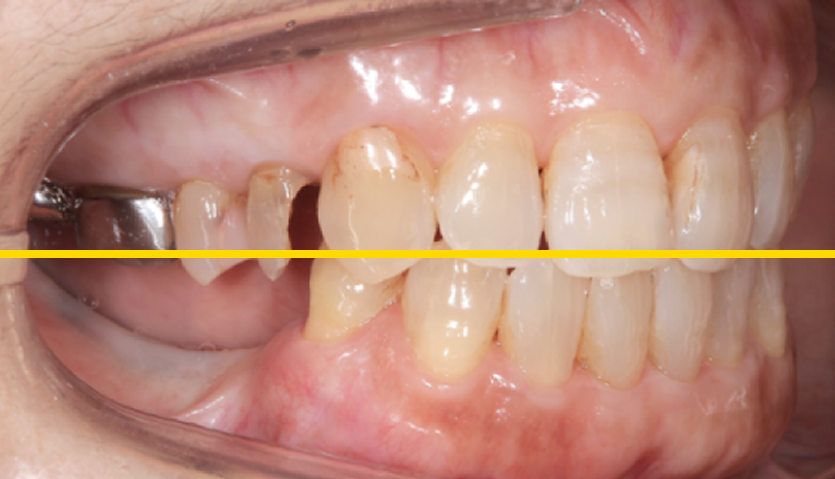

外れた左下の歯ですが、歯茎から出ている歯の部分が明らかに短く、この状態で被せ直しをしても維持力がないためすぐに外れてしまう事が予想されました。

また、奥歯がないためこの歯には噛む時の力が過剰にかかってしまいます。

この方の場合右の歯も少なく、主訴である左下の歯だけ治療をしたとしても今残っている歯も含めてどんどん悪くなることが予想されました。

このような理由で口腔全体を含めた「全顎の治療」計画を提案させていただきました。

現状残っている歯の状態から、この患者さまは「生理的咬合」であると診断し、現状噛んでいる歯の位置の修正とは行わずに、歯がないところ、歯が欠けているところを治すだけで安定すると考え治療を行っています。

この歯(黄色の印)は顎を横に動かした時に強い力が加わり、歯の周囲の組織にダメージが出ているため、力をコントロールするために歯の形を修正が必要です。